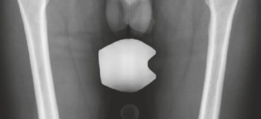

High-resolution, thin-slice computed tomography (CT) with multiplanar reconstruction is the gold standard for defining the osseous anatomy. The CT scan accurately delineates the nidus as a well-circumscribed, radiolucent focus, often containing a central fleck of mineralization, surrounded by varying degrees of sclerosis. The surgeon must meticulously map the location of the nidus relative to reliable arthroscopic landmarks, such as the medial synovial fold, the zona orbicularis, and the articular margin of the femoral head.